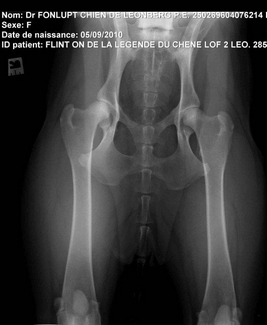

2 très très bonnes nouvelles sont arrivées ! Genkini et Flint'on ont été radiographié et les résultats sont excellents !

Ils sont AA tous les deux, aucun signe de dysplasie coxo-fémorale !